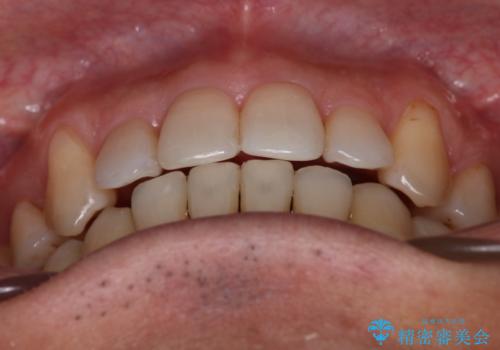

- 治療計画

叢生量が大きいため、上下顎両側4番を抜歯しました。矯正治療による歯肉退縮の著しい悪化もなく、主訴であるガタつきも改善できました。